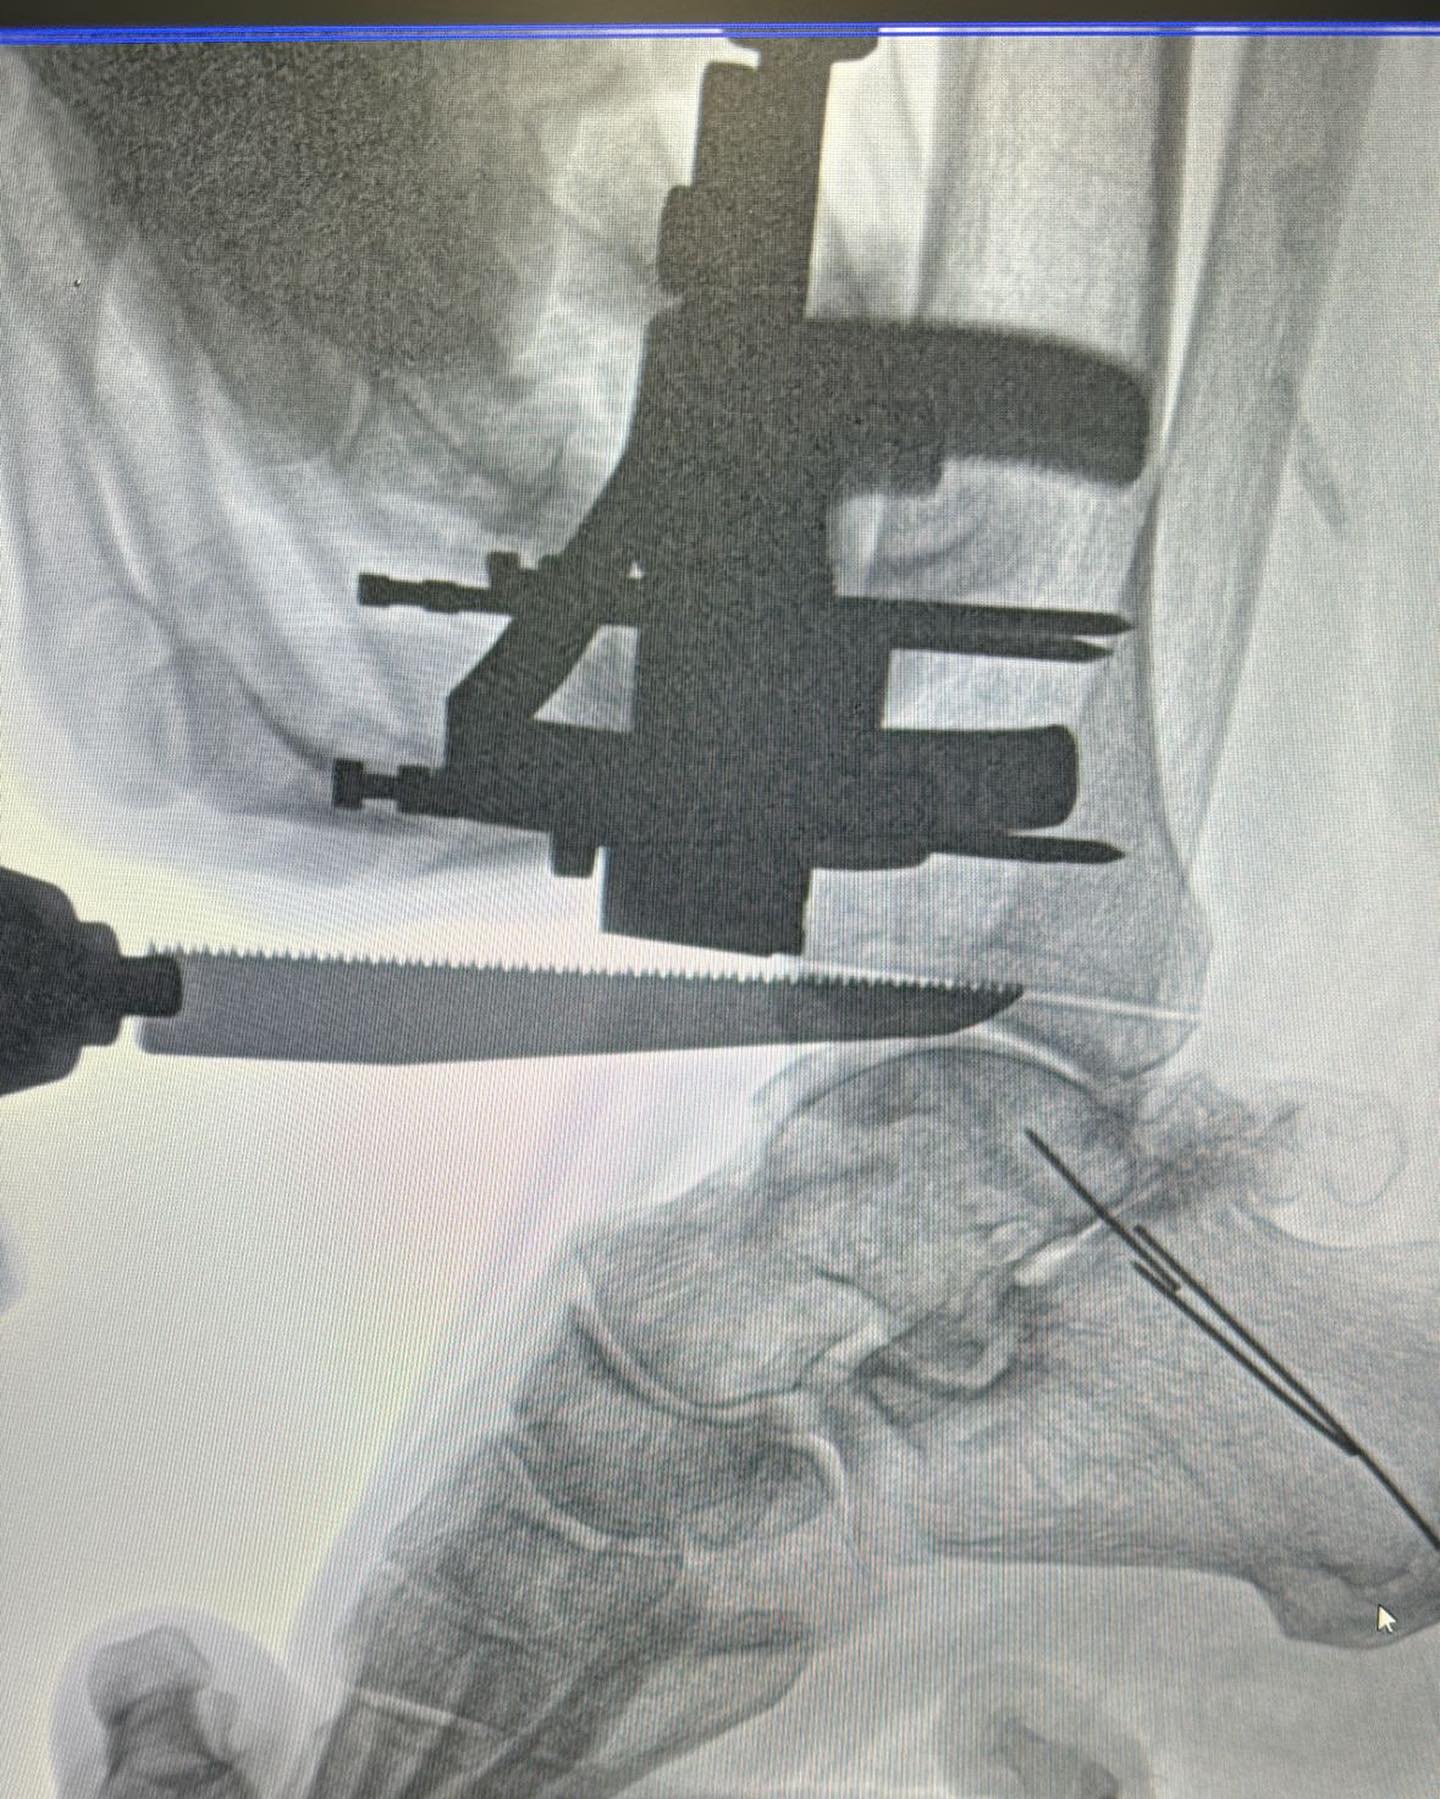

Este procedimiento quirúrgico consiste en sustituir la articulación dañada por una prótesis compuesta de metal y plástico, diseñada para restaurar la movilidad y aliviar el dolor.